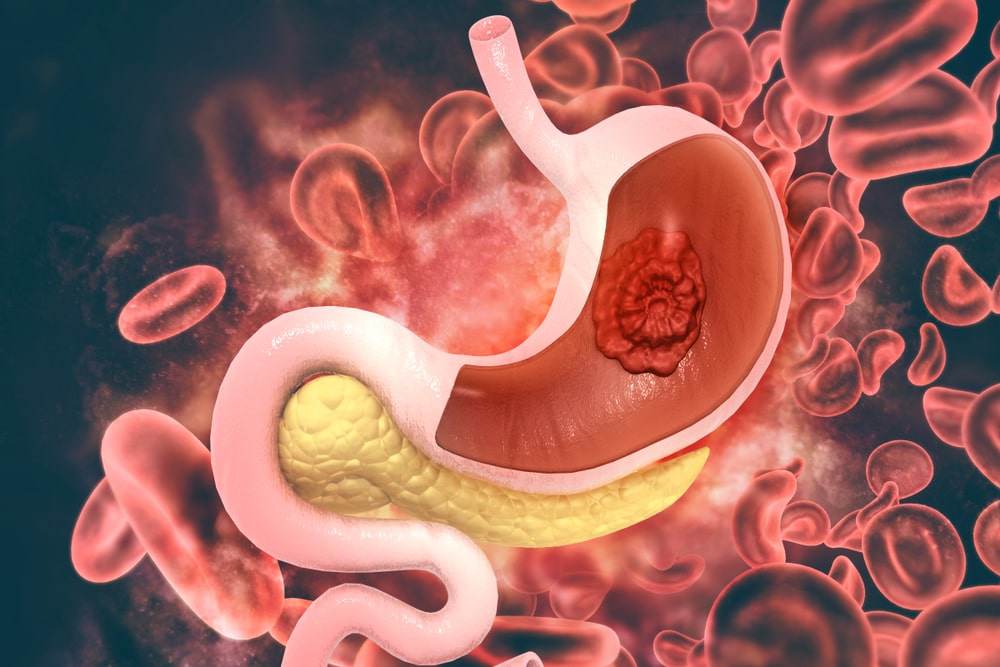

• Gastric Disorders

Acidity, Gastritis, Constipation, Diarrhea, IbS, Altherratvive Colaisi, Pain, etc.